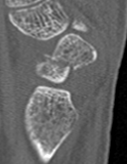

Scaphoid waist fracture 1 mm displaced

Scaphoid fracture with significant displacement

Scaphoid proximal pole fracture